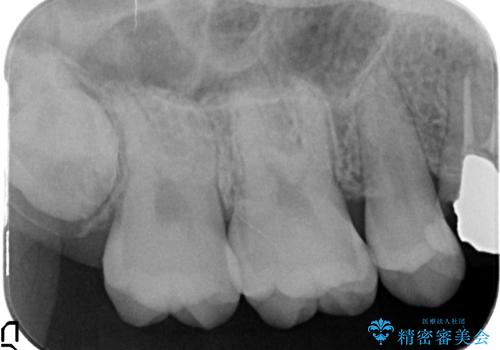

- 右上の奥歯で冷たいのもがしみるといらっしゃった方の症例です。

虫歯を除去後、セラミックインレーによる修復を行いました。

虫歯治療は虫歯の進行度によって処置が変わってきます。

虫歯が小さければ、インレー・クラウン等による修復・補綴処置を行うだけで済みます。

しかし虫歯が大きくなると神経処置や抜歯等をしなければならない場合もあります。

ですので虫歯治療においては早期発見・早期治療が肝要です。